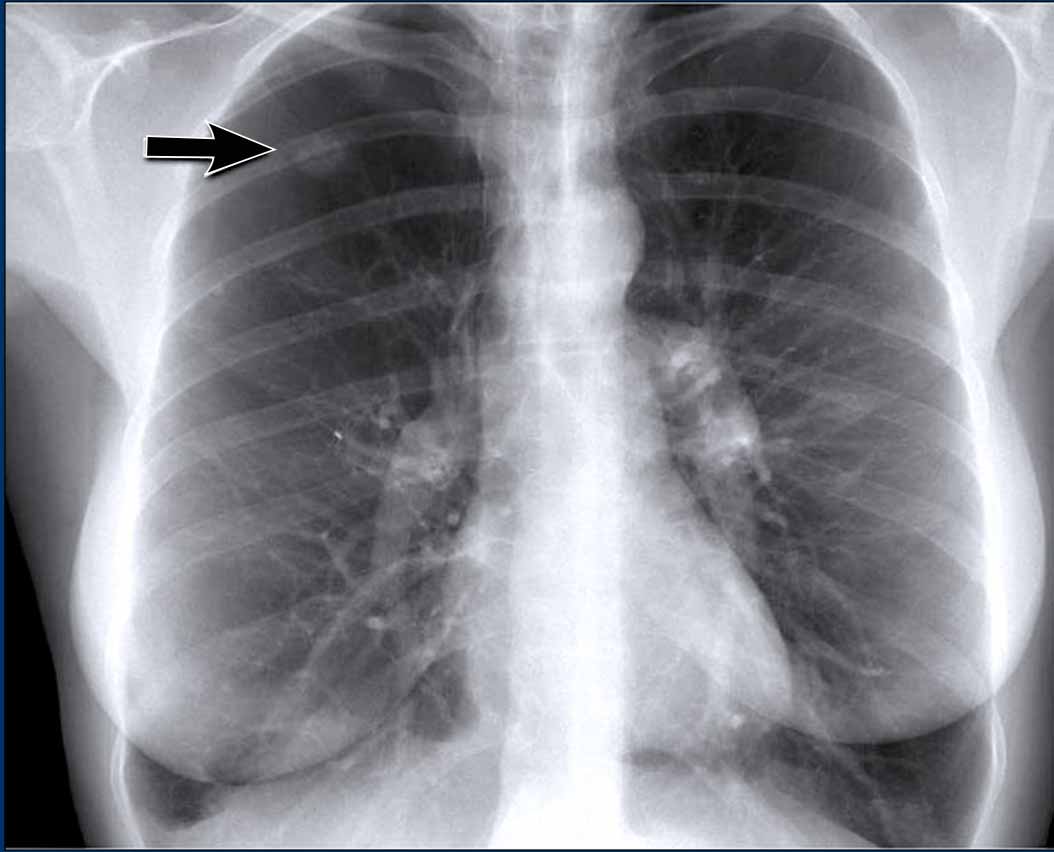

Hidden area (5): Mass Behind the First Rib

In some patients, an accessory joint at the anterior aspect of the first rib may simulate a mass, as we learned earlier.

However this area is also a "hidden zone", where true lesions can be masked.

- In this case, a small lung carcinoma was obscured by the left first rib on the PA view.

- On the lateral film, the lesion is visible in the retrosternal space.

Continue with the PET-CT...

Subsequent PET-CT imaging confirmed a hypermetabolic tumor (arrow), with metastases to the bone and liver.

- Diagnosis was confirmed via biopsy of an osteolytic metastasis in the iliac bone.

Incidental Thoracic Finding

- A subtle density is visible over the first rib in the left upper lobe, located in the so-called "hidden area".

- This was subsequently diagnosed as a primary lung carcinoma.